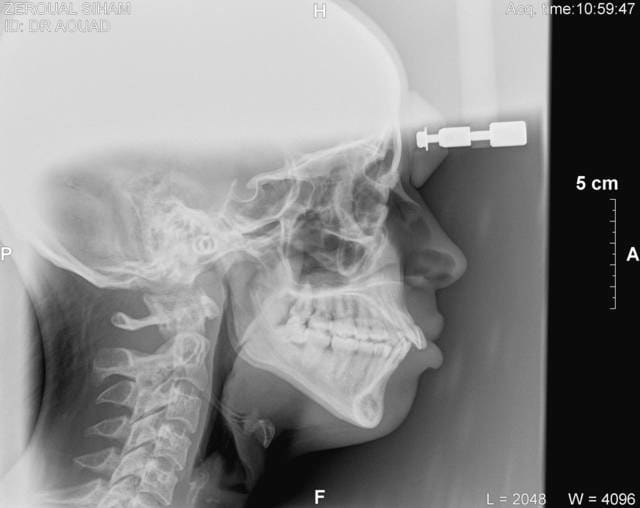

Je me permets d'intervenir car le sujet est tres interessant, tres important et peut compromettre tout un traitement orthodontique. Avant de decider d'ingresser les incisives il faut deja poser le bon diagnostic differentiel. S'agit-il d'une vraie supraclusion incisives? d4origine maxillaire seule, mandibulaire seule ou mixte? Est-ce une infralaterale qui developpe une fausse supraclusion incisive? ou bien c'est un probleme mixte?

La question suivante sera la suivante: doit-on faire une ingression pure des incisives? ou bien il faut chercher une action combinée d'ingression incisive et d'egression des dents laterales?

Du point de vue biomecanique tout arc continu va niveller une arcade dentaire en agissant sur le secteur incisif et les secteurs lateraux en même temps!!! Esc-ce souhaitable sur le plan occlusal, dentaire, squelettique, fonctionnel et esthetique???? Cela fait beaucoup de questions à repondre avant de placer un arc n'importe lequel et n'importe comment.

En deux mots si l'ingression incisive pure est recherchée il n'y a que l'arc de base de Ricketts, ou arcs similaires. Quand à l'arc de base de Ricketts qui est un systeme extra ordinaire pour ingresser les incisives en denture mixte et definitive, il a un inconvinient c'est d'estre relativement difficil à maitriser sans une formation adequate. On ne peut pas l'apprendre en lisant toutes la litterature orthodontique.

17/06/2011 à 13h45

on a fait des TP pour l arc utilitaire de ricketts

la patiente a un sourire gingival comment voulez vous que je n'ingresse pas ses incives

pour ça j'ai utilisé un 16 NITI courbe de spee inversé

Personne n'a contredit le besoin de faire une ingression, mais est-ce que tu connais bien les regles d'or pour faire une bonne ingression des incisivies?

1- Il faut corriger l'axe avant de faire l'ingression, cela fait partie de la regle TVA à ne pas manquer!

2- Pour faire de l'ingression pure il faut un arc de base obligatoirement, ou similaire.

3- Pour faire un arc de base superieure il faut savoire quel fil et quelle section, en bas et en haut

4- Pour faire un bon arc de base d'ingression il faut repondre à 12 questions en ce qui concerne les informations à donner à l'arc avec les reponses oui, non combien et pourquoi. Est-ce que tu t'es posé ces questions??

5- Si ton instructeur ne fait pas la technique de Ricketts dans son cabinet et ne maitrise pas parfaitement cette phylosophie il sera incapable de te l'enseigner correctement, avec tout le respect à tes profs.

> pour ça j'ai utilisé un 16 NITI courbe de spee inversé

Ce système provoque obligatoirement une egression des secteurs lateraux!! 0.5 mm d'egression laterale annule l'avantage de 2 mm d'ingression incisive!!! est-ce que tu le sais bien???